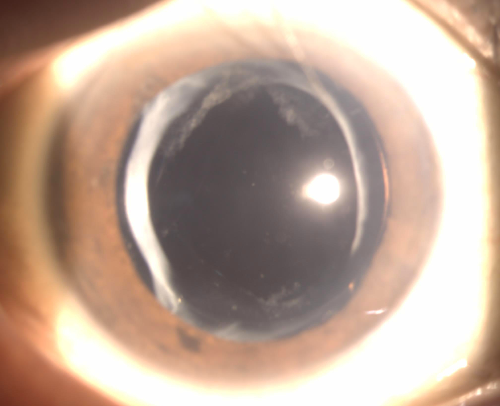

YAG레이저 치료 후에 훨씬 밝아졌다고 하십니다.

반대편도 추후 레이저가 필요한 상황입니다.